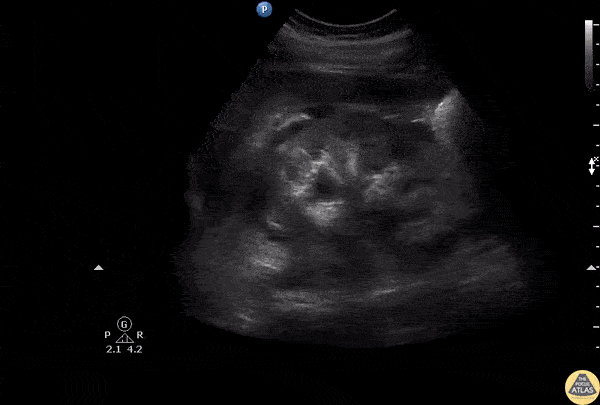

Longitudinal view of the kidney reveals an anechoic space adjacent to the kidney, likely due to a urinoma secondary to a calyx rupture. Image courtesy of Robert Jones DO, FACEP @RJonesSonoEM Director, Emergency Ultrasound; MetroHealth Medical Center; Professor, Case Western Reserve Medical School, Cleveland, OH View his original post here